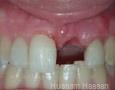

Ridge Augmentation > Combined Horizontal & Vertical

Summary Case - By Hussam Hassan

Pictures

Surgery